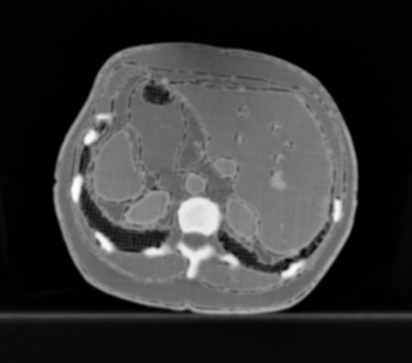

3.1.4 Example 3: Scanner settings impact in IQ

Here, we show an example of quality differences with acquired CT data from a realistic silicone phantom fabricated with multi-material extrusion 3D printing technology (citep \@BBN(Hatamikia et al., 2023)). The phantom model was derived from an abdominal CT and was fabricated with realistic radio density values which could mimic imaging properties of soft tissues in CT.

For the reference image, the anatomical phantom was scanned with the standard clinical CT protocol from SOMATOM Definition AS scanner, Siemens Healthineers, Erlangen Germany (tube current time product 70mAs for samples and 150mAs for anatomical phantom, tube voltage 120kVp, slice thickness 0.60mm, pixel spacing 0.77mm, iterative reconstruction kernel J30s). Additional scans with varying kVp values (80/100/120) as well as varying slice thickness (0.6/2mm) were also performed to assess the effect of the parameters on the image quality. We observed that changing kVp and slice thickness resulted in different image quality, where higher kVp and smaller slice thickness give the best visual result.

Refer to caption

(a) Reference

(b) (26.3, 0.88, 0.07)

(c) (28.2, 0.95, 0.03)

Figure 4: Comparison of image acquisition settings, (a) reference image with best chosen parameter setting (0.6mm and 120kVp), (b) preserves more detail (0.6mm and 80kVp) than (c) which is more smoothed (2mm and 100kVp). PSNR/SSIM misjudge the visual quality, LPIPS yields reasonable quality scores here.

FR-IQA mismatches

Although all IQA measures yield a better value for the image shown in Figure 4(c), a higher visual correspondence with the reference image can be seen in Figure 4(b) despite the black shadow in the bottom left corner. The image in Figure 4(c) with lower kVp yields a result that is too smooth in comparison to the reference. This yields another CT example where the IQA measures have been mislead by quality properties that are not relevant for the clinical application.